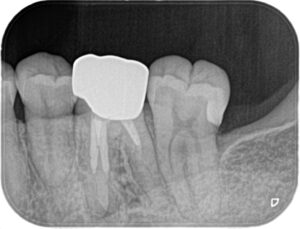

虫歯の部分のみ除去し、コンポジットレジンで充填しました。

当院ではできる限り大きく削らない治療を心がけています(^^)/